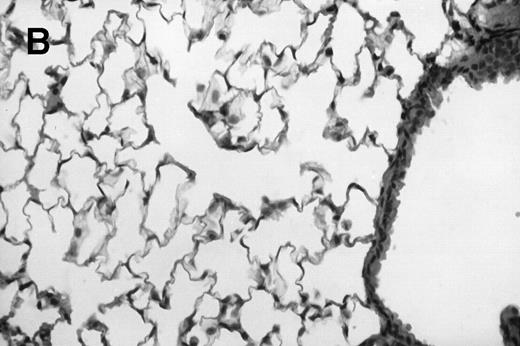

Allogeneic transplanted mice (B10.BR → CBA) with GVHD and, as controls, allogeneic transplanted mice without GVHD and syngeneic transplanted mice (B10.BR → B10.BR) were infected intranasally with HSV-1 at 12 weeks after transplantation. As an additional control, age-matched normal CBA mice were infected as well. Histological examination of lungs was performed in mock-infected mice and in mice at day 7 after infection. Allogeneic transplant recipients with GVHD showed increased pathology (Fig 1). Scores reflecting the periluminal histopathologic changes were significantly higher (P = .05; Student's t-test) in allogeneic transplant recipients with GVHD, when compared with control mice (Fig 2). The periluminal histopathologic scores were also higher in allogeneic transplant recipients with GVHD, when compared with normal CBA mice, at days 4, 10, and 14 after infection (data not shown). No significant differences were observed in the scores reflecting the parenchymal histopathologic changes (data not shown). Because the results in syngeneic transplanted mice were very similar to those in allogeneic transplanted mice without GVHD, the latter, which are the most appropriate control for procedural effects and for the effect of GVHD, and normal CBA mice, were used as controls in further experiments.

Allogeneic transplant recipients with GVHD showed increased pathology. Photomicrographs of lung sections stained with hematoxylin and eosin show evidence of increased pathology in infected allogeneic GVHD mice. (A) Normal CBA, mock-infected, original magnification × 25; (B) normal CBA, mock-infected, original magnification × 100; (C) normal CBA, infected, original magnification × 40; (D) normal CBA, infected, original magnification × 100; (E) allogeneic GVHD, mock-infected, original magnification × 10; (F) allogeneic GVHD, mock-infected, original magnification × 75; (G) allogeneic GVHD, infected, original magnification × 10; (H) allogeneic GVHD, infected, original magnification × 100.